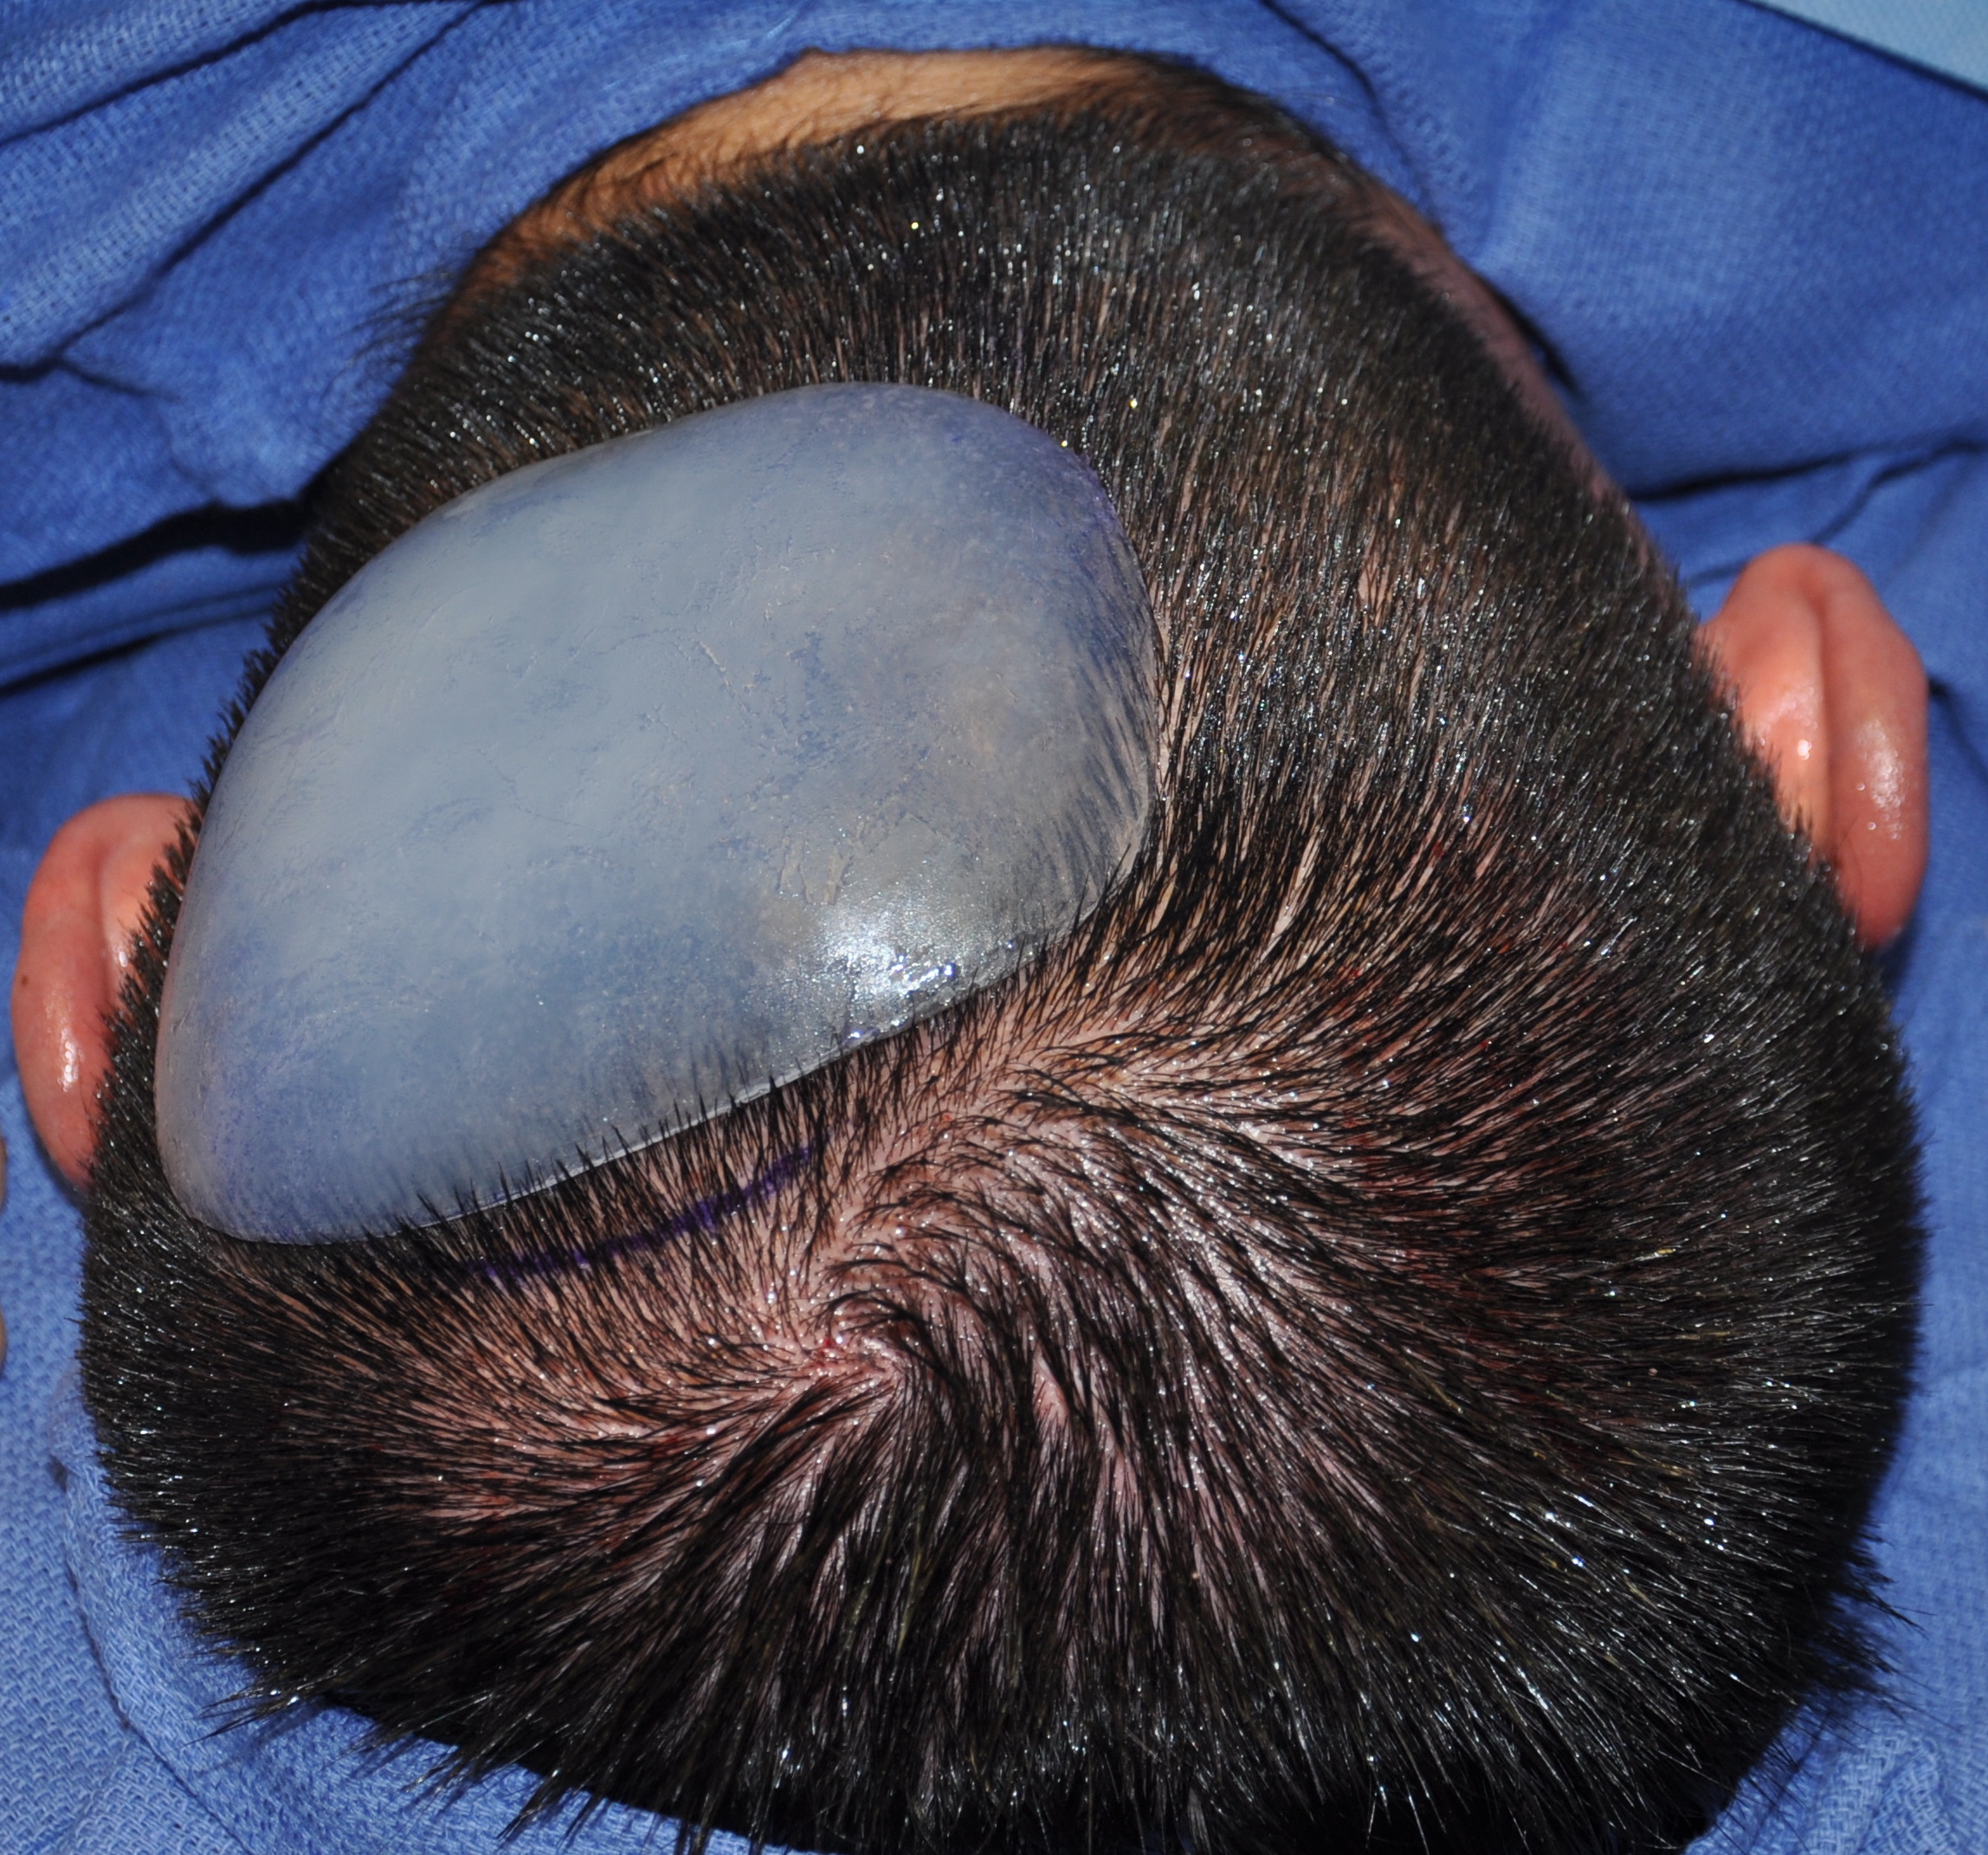

Scalp avulsion due to traumatic injury which left a large patch of non-hair bearing scalp.

Hair bearing scalp reconstruction using a first stage tissue expanders and second stage scalp scar removal.

Scalp avulsion due to traumatic injury which left a large patch of non-hair bearing scalp.

Hair bearing scalp reconstruction using a first stage tissue expanders and second stage scalp scar removal.